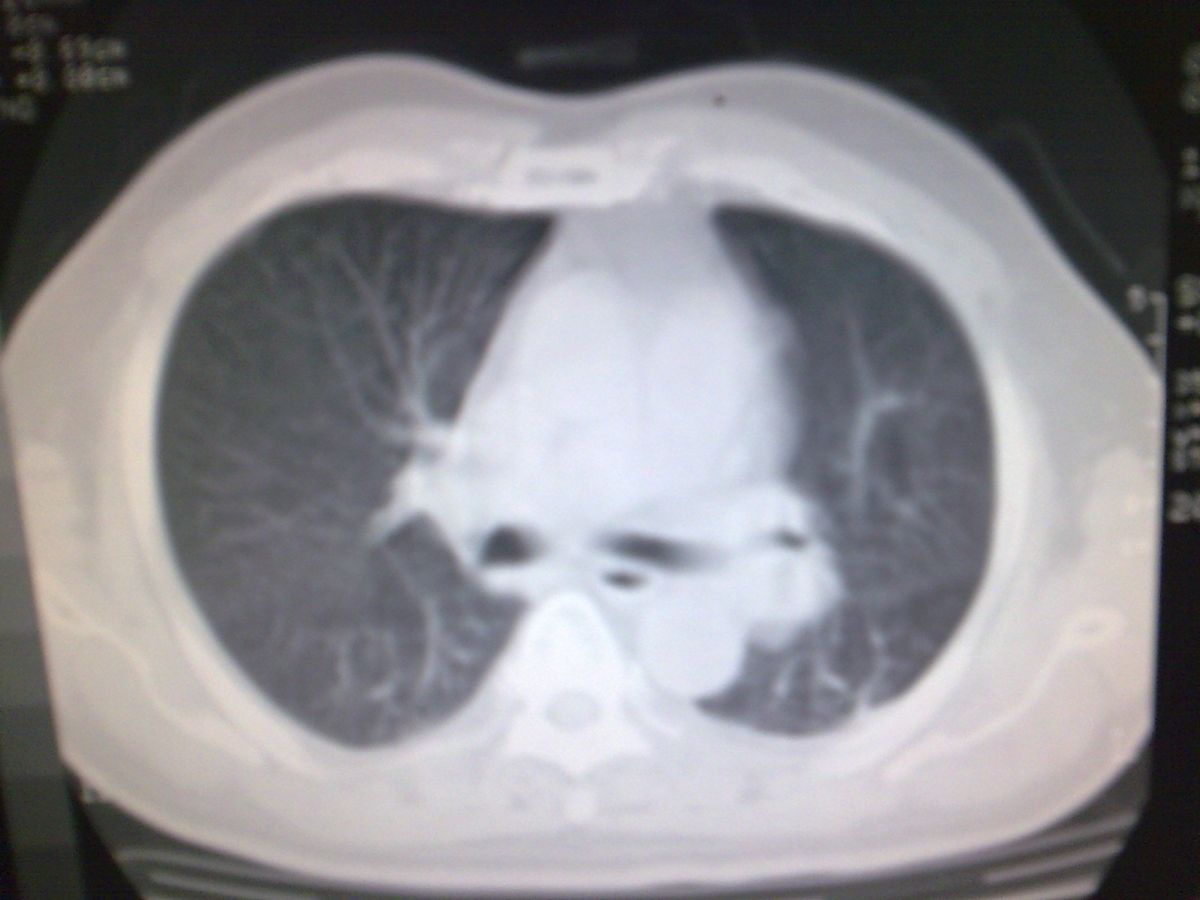

标题: CT19282:男性,70岁,咳血, [打印本页]

标题: CT19282:男性,70岁,咳血,

图片少了些,考虑周围性肺癌

考虑周围性肺癌

周围型肺癌。

考虑左下肺周围性肺癌。

考虑左下周围型肺癌可能性大。

考虑左肺下叶周围型肺癌可能。